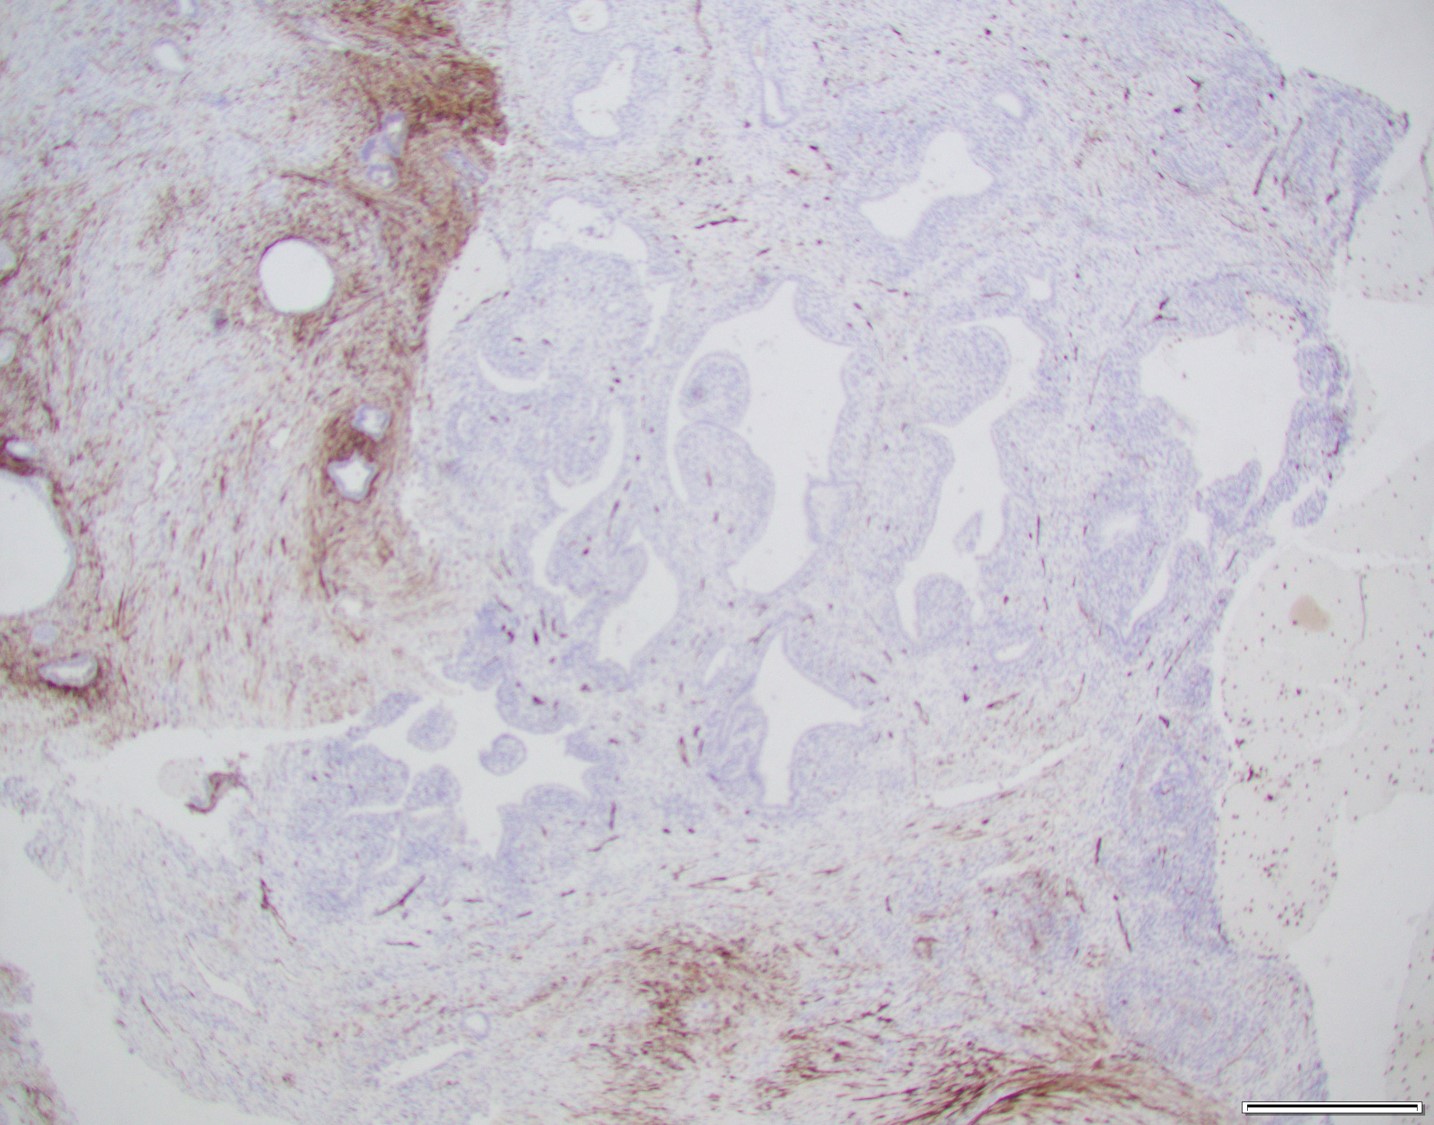

There are two components comprising this specimen, which are focally intimately associated with one another. The first component consists of endometrial glands and stroma surrounded by smooth muscle bundles, which in the proper clinical setting could represent a benign adenomyomatous polyp. The second component consists of a biphasic process of benign glands and stroma with a phyllodes-like architecture. The stroma surrounding the glands shows periglandular "cuffing" with very low-grade atypia. There is increased mitotic activity (greater than 2 mitoses/10 HPF) in the areas with the phyllodes-like architecture. Immunohistochemical staining showed two distinct staining patterns in the two components. The adenomyomatous polyp component showed CD10 highlighting endometrial stroma in the adenomyomatous areas with surrounding smooth muscle bundles positive for caldesmon and desmin while the stroma in the phyllodes-like area was positive for desmin and caldesmon but was negative for CD10. The patient was treated with a hysterectomy, where there was minimal focal residual disease identified.